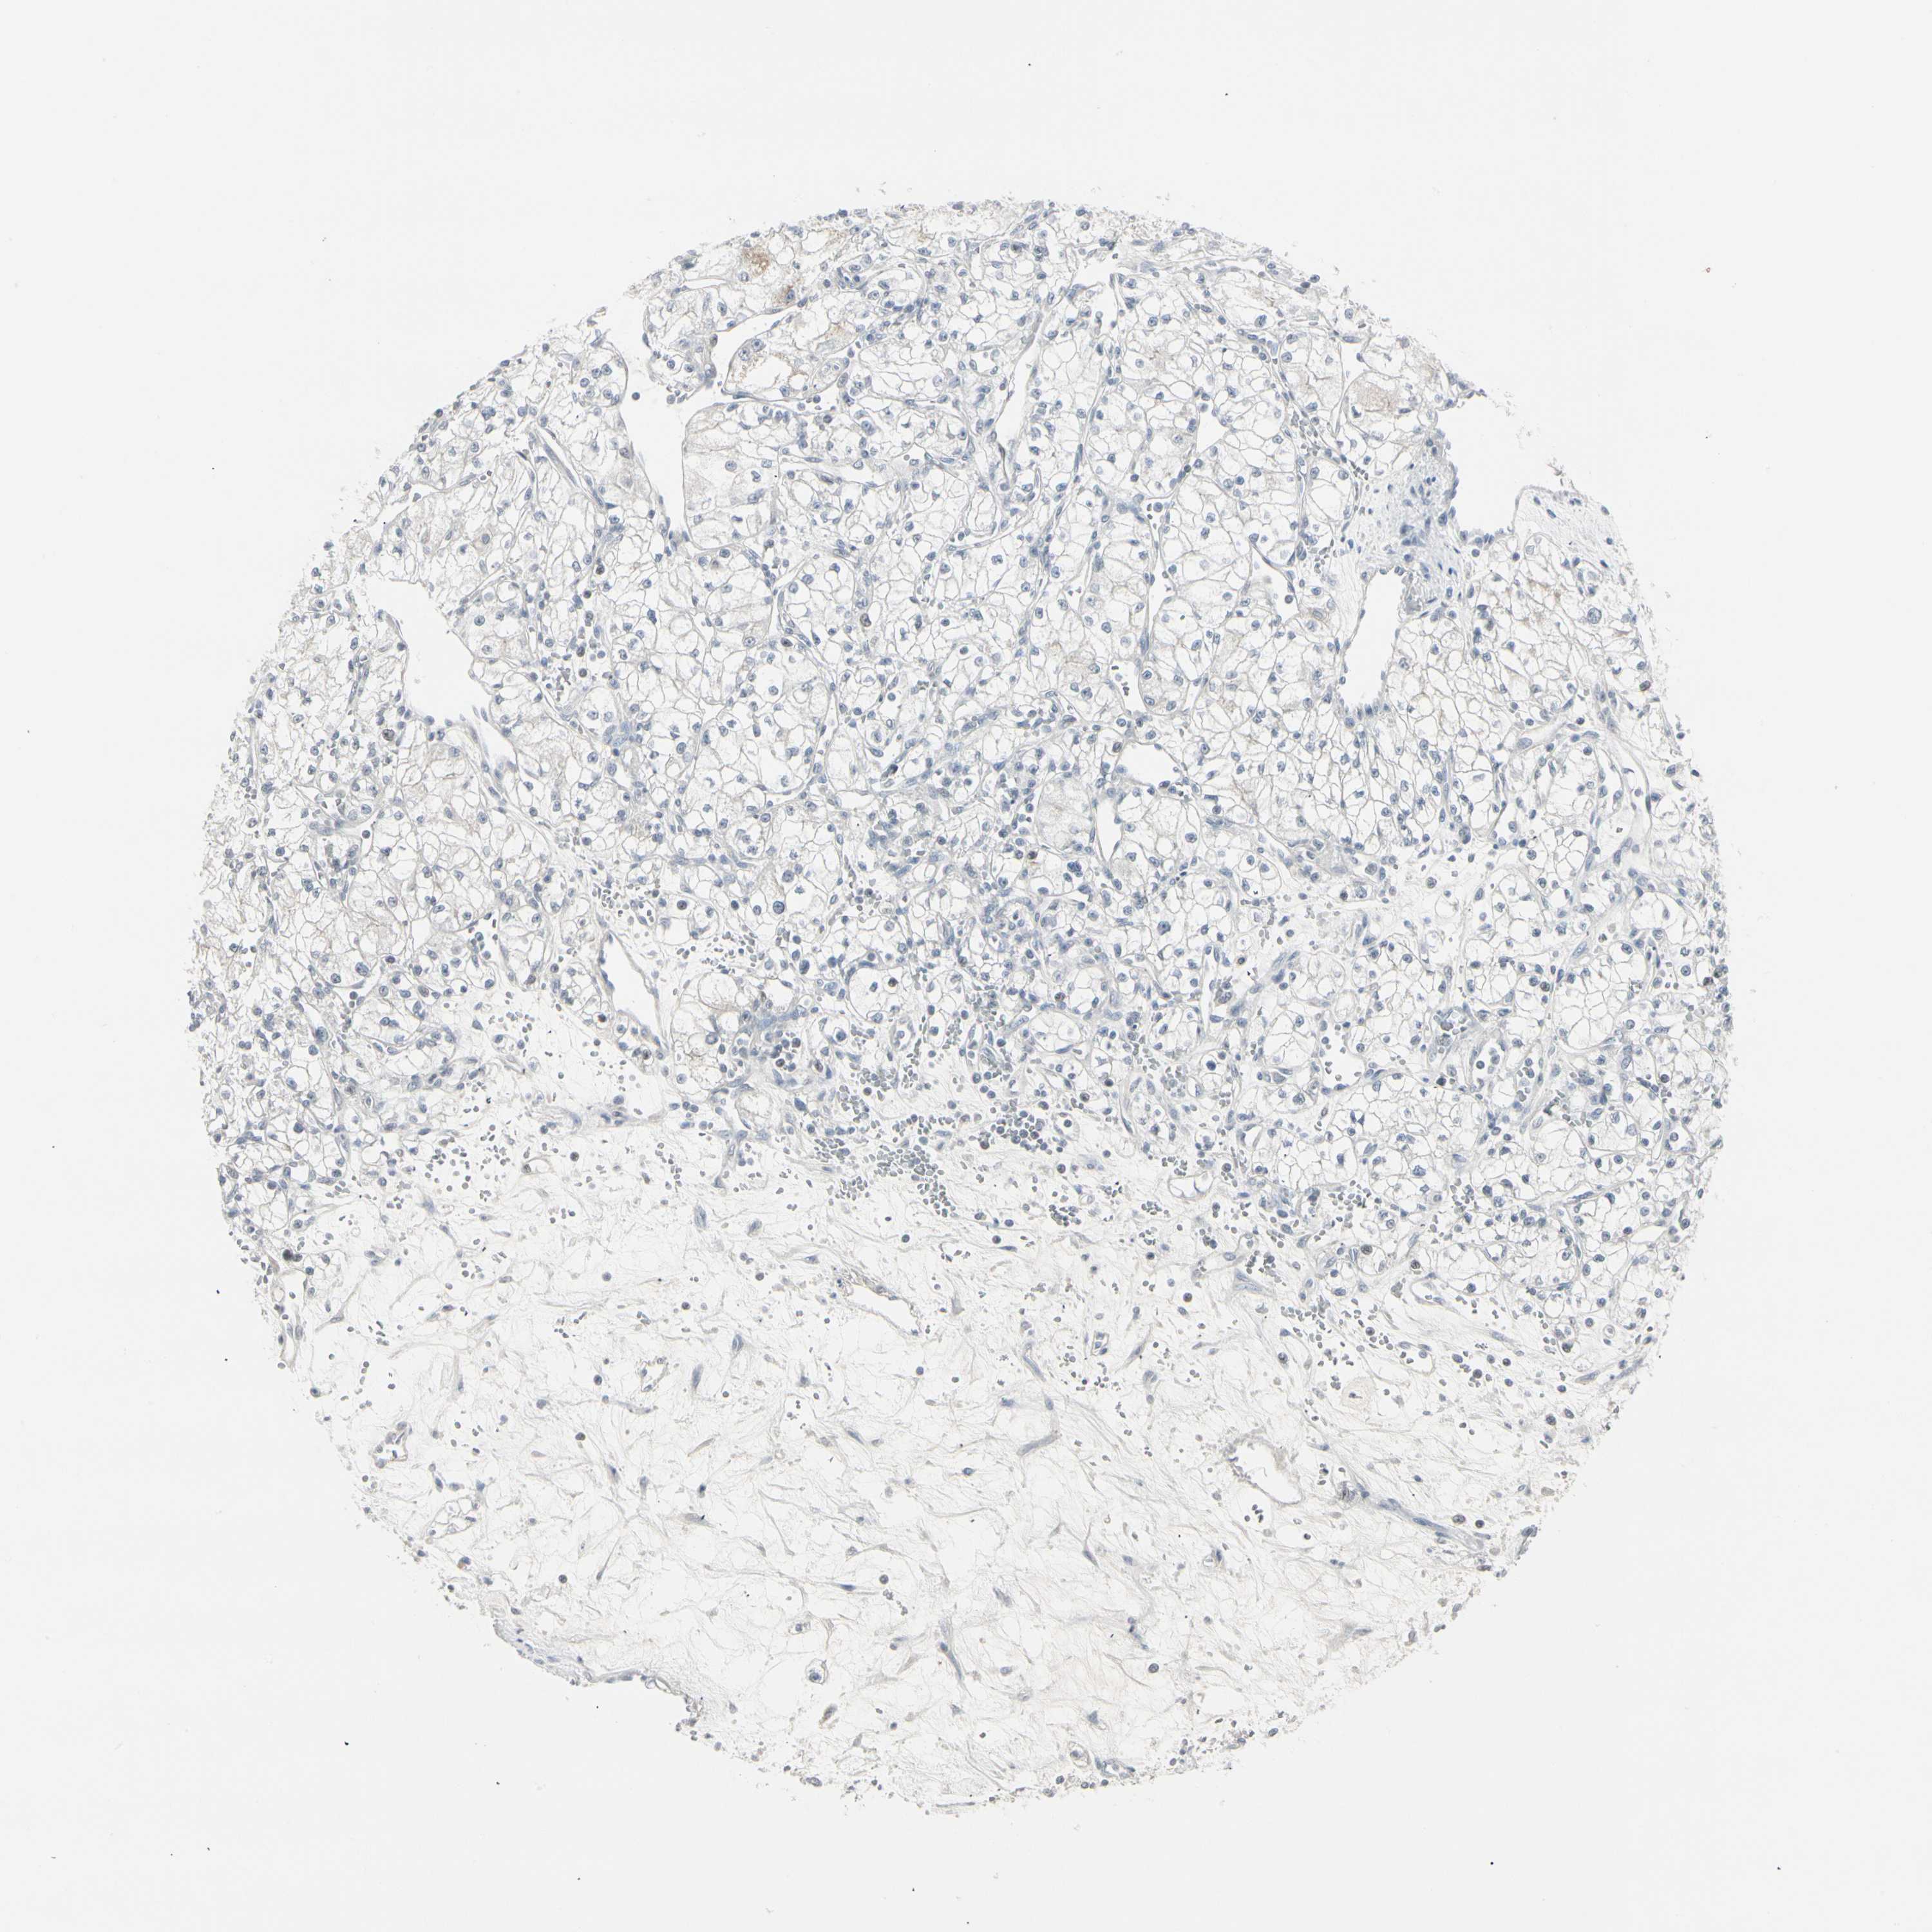

CANCER RENAL CANCER Show tissue menu

KICH TCGA KIRC TCGA KIRC VALIDATION KIRP TCGA PROTEIN RCC CPTAC PROTEIN EXPRESSION